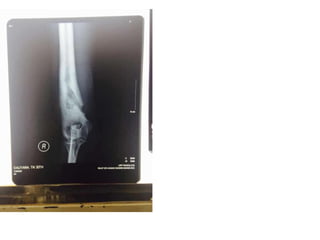

• Tampak lesi litik dan

sklerotik pada 1/3 distal os

humerus dan 1/3 proximal

os radius.

• Tampak lesi periosteal pada

1/3 distal os humerus

kanan dan 1/3 proksimal os

radius kanan

• Kesan: menyokong suatu

osteomielitis kronis

Foto elbow